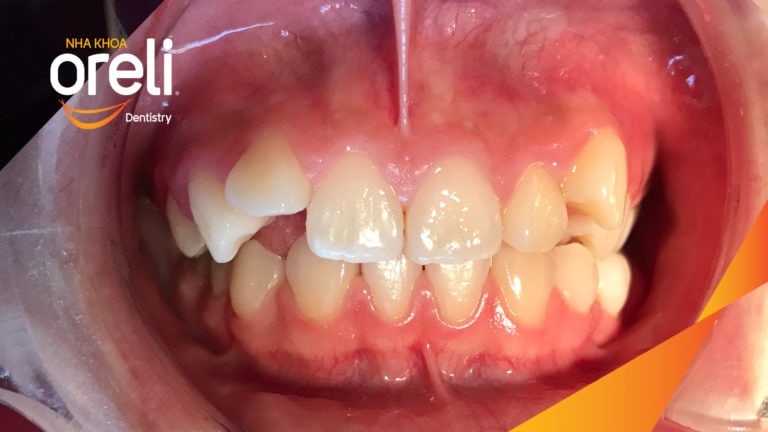

Ca niềng chỉnh chen chúc sai khớp cắn hạng 3 móm nhẹ – Kết quả thực tế ở Oreli Niềng răngChen chúcMóm Xem thêm